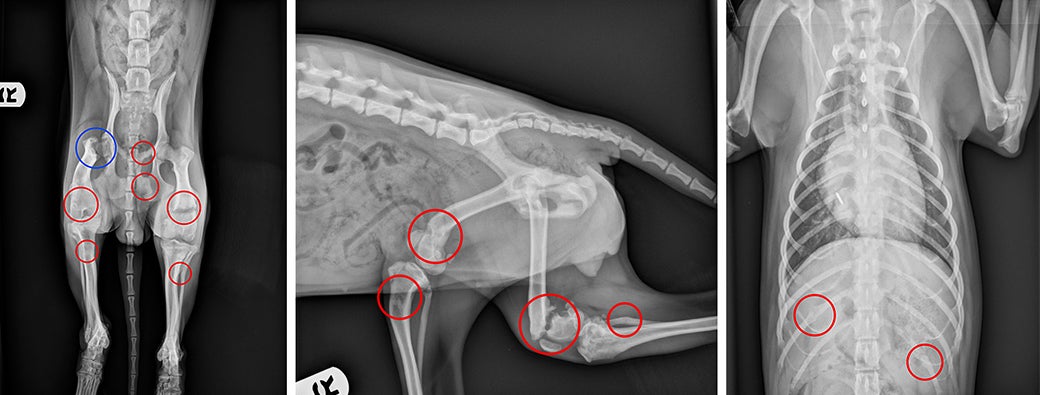

Circles on X-rays indicate Beeps’ multiple fractures. Dr. J’mai Gayle restored mobility in Beeps’ right hip (blue circle) by removing pieces of her fractured femur, as well as realigning her right kneecap.

Dr. J’mai Gayle, Director of Surgery at the ASPCA Animal Hospital, did not attempt to repair any of the fractures because they were too old. But she did perform a femoral head osteotomy, or FHO, to surgically remove the pieces of Beeps’ right fractured femur, which helped restore mobility in her right hip. Dr. Gayle also surgically realigned Beeps’ right kneecap, or patella, which was dislocated.

“Beeps had old fractures on her left and right distal femurs—the area of the leg just above the knee joint—and fractures of both tibias,” says Dr. Gayle. “This was such a horrible case, so many fractures.”